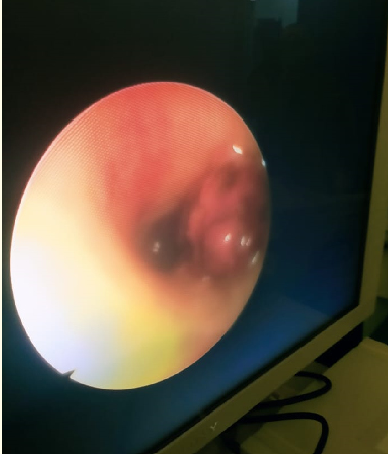

Tracheal Tear Post Appendectomy

Abdu Hasan Ayoub, Mohammed Mohmmed Haroon, Ohemu Alexander Akogwu, Nasir Ali Alharbi, Alaa El Din Sadek Zidan, Qada Bin Omar, Hasan Ahmed Wadaani, Naief Ali Domary, Majid Ibrahim Hakami, Raoom Abdu Ayoub, Imtenan Ali Oberi and Mostafa Jalal Mostafa. 5(10): 54-61.